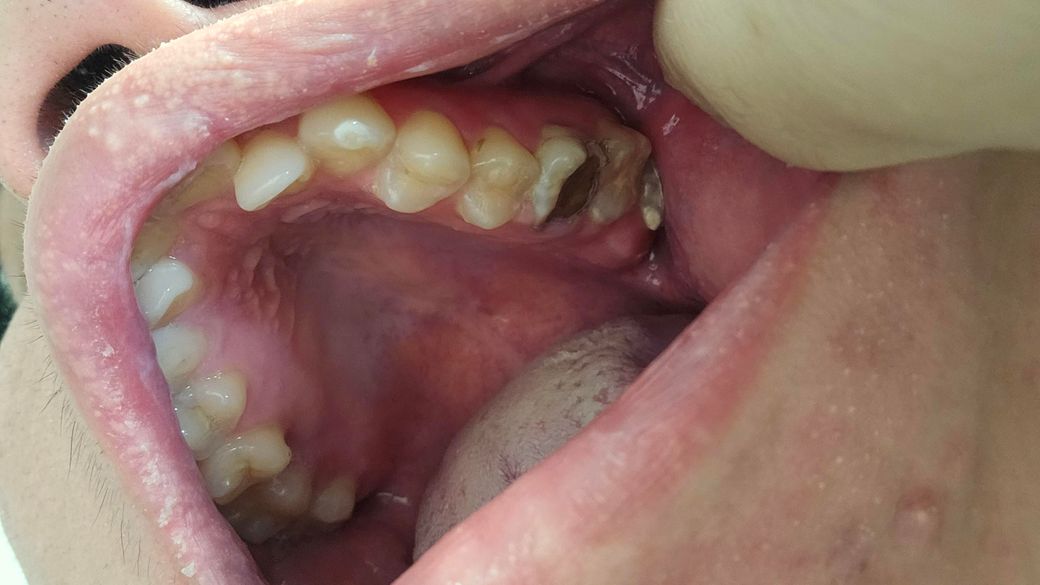

제가 다음주토요일11월9일 치과 갔는데요 조금 늦게 갔는것가요 다음주 토요일 치과 예약 꼭해야하는것가요? 늦게갔도 치료할수있나요 제이빨상태가상태이면

• 1번 째 사진

이미치아 상태가 안좋기 때문에 2주 후에 간다고 해서 치료 방법에 크게 차이가 날 것 같진 않습니다.

육안상으로 아래 치아는 발치를 하셔야될것같지만 위쪽 치아는 엑스레이를 찍어보고 치료를 할지 발치를 할지 결정해야될것같습니다.

치아에ㅐ 이미 충치가 많이 진행된것으로 보입니다.

빠른 치료가 필요할것으로 보이기 때문에 가능한 빠른 시간내에 치과에서 진료를 받아보는것이 좋습니다.

치과는 당일 진료가 어려울 수 있습니다. 예약 반드시 하세요. 발치 가능성 있는 치아들입니다.